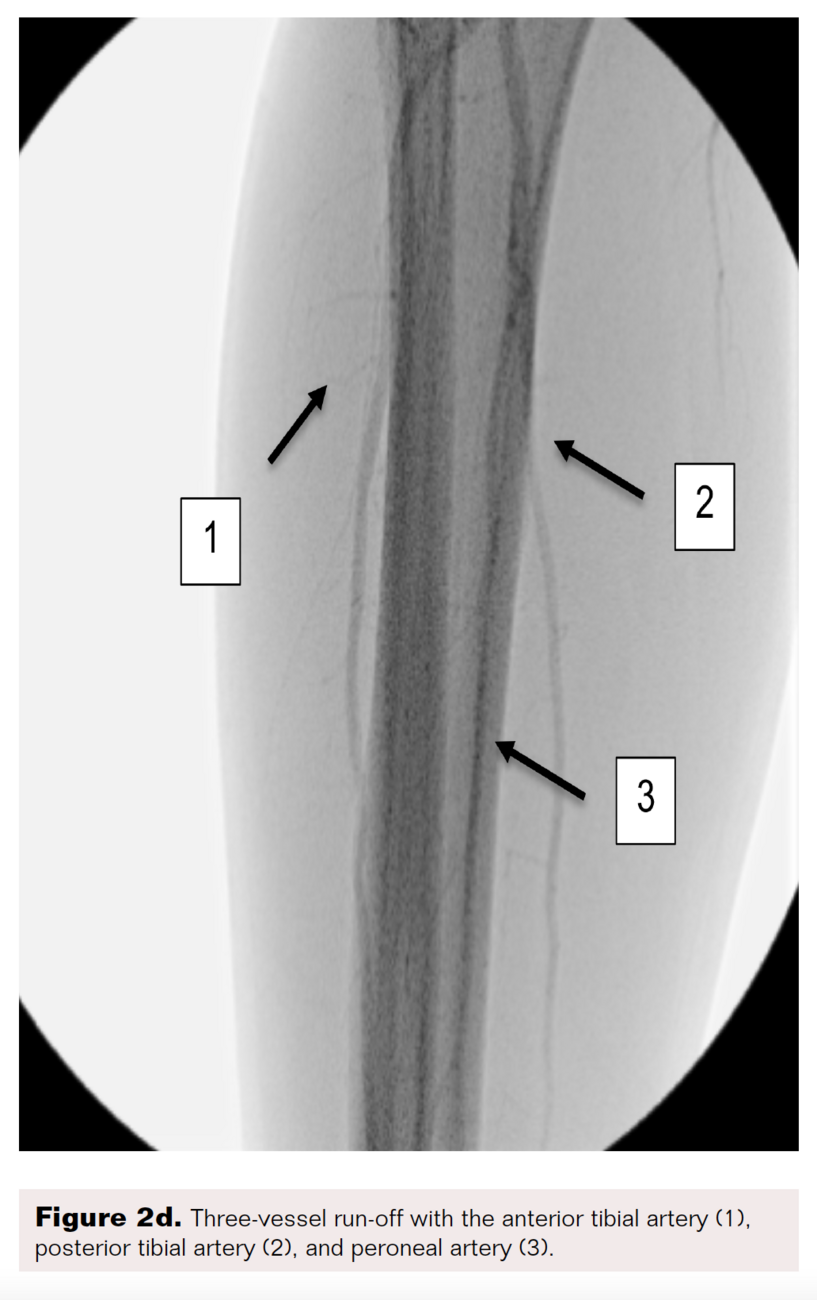

A right lower-extremity angiogram was performed using ultrasound guidance for antegrade access of the proximal superficial femoral artery (Figure 2A). Fluoroscopic acquisition demonstrated no significant disease in the superficial femoral artery (Figure 2B) and popliteal artery (Figure 2C), with no significant stenosis seen in the anterior tibial artery, PTA, and peroneal artery (Figure 2D). Pedal angiography demonstrated a complete pedal-plantar loop formed by the DPA and the lateral plantar artery (LPA) (Figure 2F).